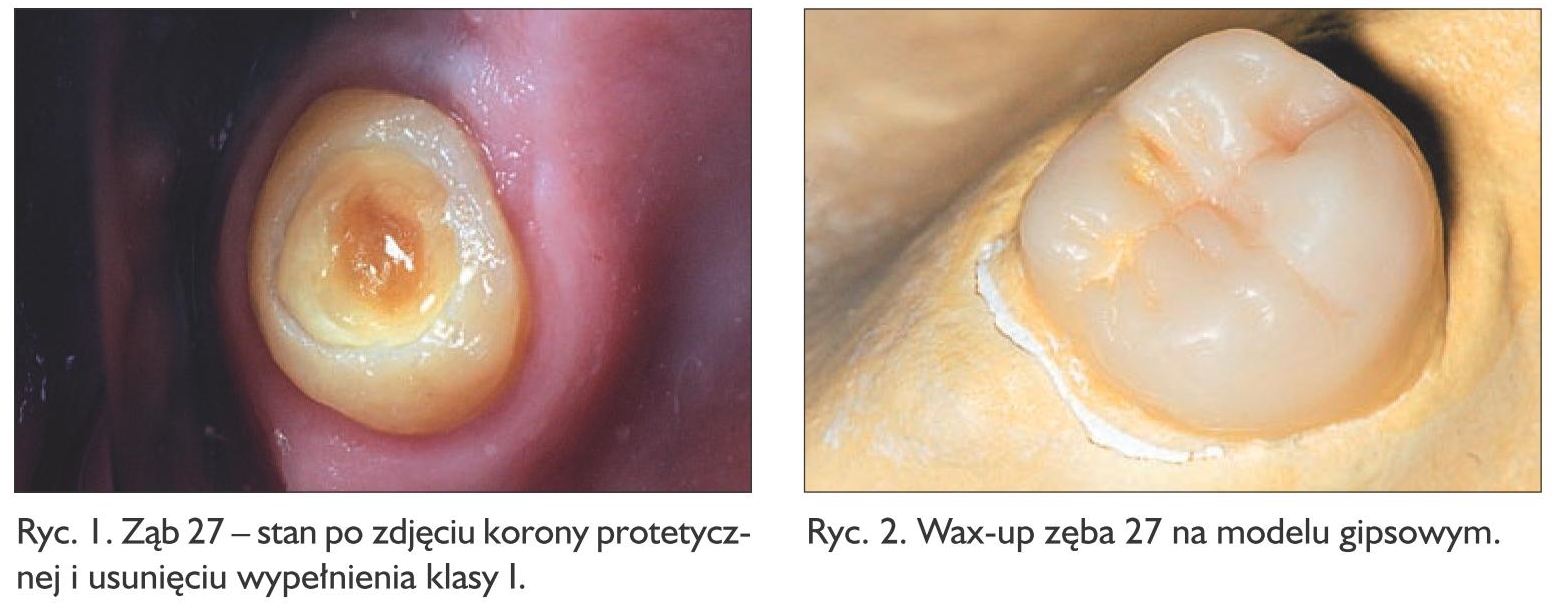

W pierwszej kolejności usunięto kamień nazębny zalegający poniżej brzegu korony i poddziąsłowo. W zębie, na powierzchni zgryzowej, znajdowało się rozszczelnione wypełnienie kompozytowe klasy I. Pozostałe powierzchnie zęba nie były objęte próchnicą. Reakcja miazgi była prawidłowa, ząb nie reagował nadwrażliwością i bardzo dobrze rokował pod względem utrzymania w kości. W takim wypadku można by się pokusić jedynie o wymianę wypełnienia, jednak ząb 27 miał stanowić podparcie dla planowanej protezy szkieletowej w szczęce, stąd potrzebne było nadanie mu retencyjnego kształtu. Wspólnie z pacjentką podjęto decyzję o wykonaniu pracy metodą półpośrednią z wykorzystaniem materiału kompozytowego, aby uniknąć zbędnego szlifowania zęba, a tym samym utraty zdrowej tkanki, już raz oszczędzonego, szkliwa.

Usunięto nieszczelne wypełnienie klasy I, ubytek oczyszczono z tkanki próchnicowej (ryc. 1). Na podstawie wax-upu (ryc. 2) wykonano transparentny indeks silikonowy (Elite Glass, Zhermack), który przymierzono na opracowany ząb 27 (ryc. 3). Indeks zdjęto z zęba, ubytek i ściany zewnętrzne posmarowano cienką warstwą żelu glicerynowego. Do indeksu nałożono materiał kompozytowy Estelite Posterior PA3 (Tokuyama Dental), dokładnie skondensowany, w jednej warstwie. Indeks z nałożonym niespolimeryzowanym materiałem wprowadzono ponownie na ząb, dociskając tak, by uzyskać sprawdzone wcześniej stabilne położenie, a tym samym doprowadzić do wypłynięcia nadmiarów kompozytu. Zastosowany materiał kompozytowy umożliwia wygodną i spokojną pracę, bez ryzyka wcześniejszej polimeryzacji, a jego właściwości fizyczne dają pewność co do odpowiedniej wytrzymałości mechanicznej wykonanego uzupełnienia. Po usunięciu nadmiarów materiał spolimeryzowano światłem lampy polimeryzacyjnej, poprzez transparentny indeks silikonowy, 60 sekund z każdej strony. Zdjęto indeks, a każdą powierzchnię znajdującej się na zębie odbudowy dodatkowo doświetlono. Następnie odbudowa została ostrożnie podważona zgłębnikiem w celu jej usunięcia z ubytku. Uwolnioną pracę (ryc. 4) dodatkowo doświetlono od strony wewnętrznej. Wykonaną odbudowę odtłuszczono, przemywając ją alkoholem izopropylowym. Gdy stosuje się metodę półpośrednią, nie stanowią problemu wycienienia odbudowy, w tym wypadku widoczne na powierzchni zgryzowej i przedsionkowo. Były one odwzorowaniem cienkiej warstwy wosku nałożonego na modelu, co wynikało z sytuacji klinicznej. Gdyby jednak – w innym przypadku – istniała potrzeba nadbudowy takich miejsc (np. gdyby niedomiar powstał na skutek uszkodzenia pracy przy jej uwalnianiu z zęba), na kolejnym etapie mogłyby one zostać uzupełnione tym samym materiałem kompozytowym, z którego praca została wykonana.